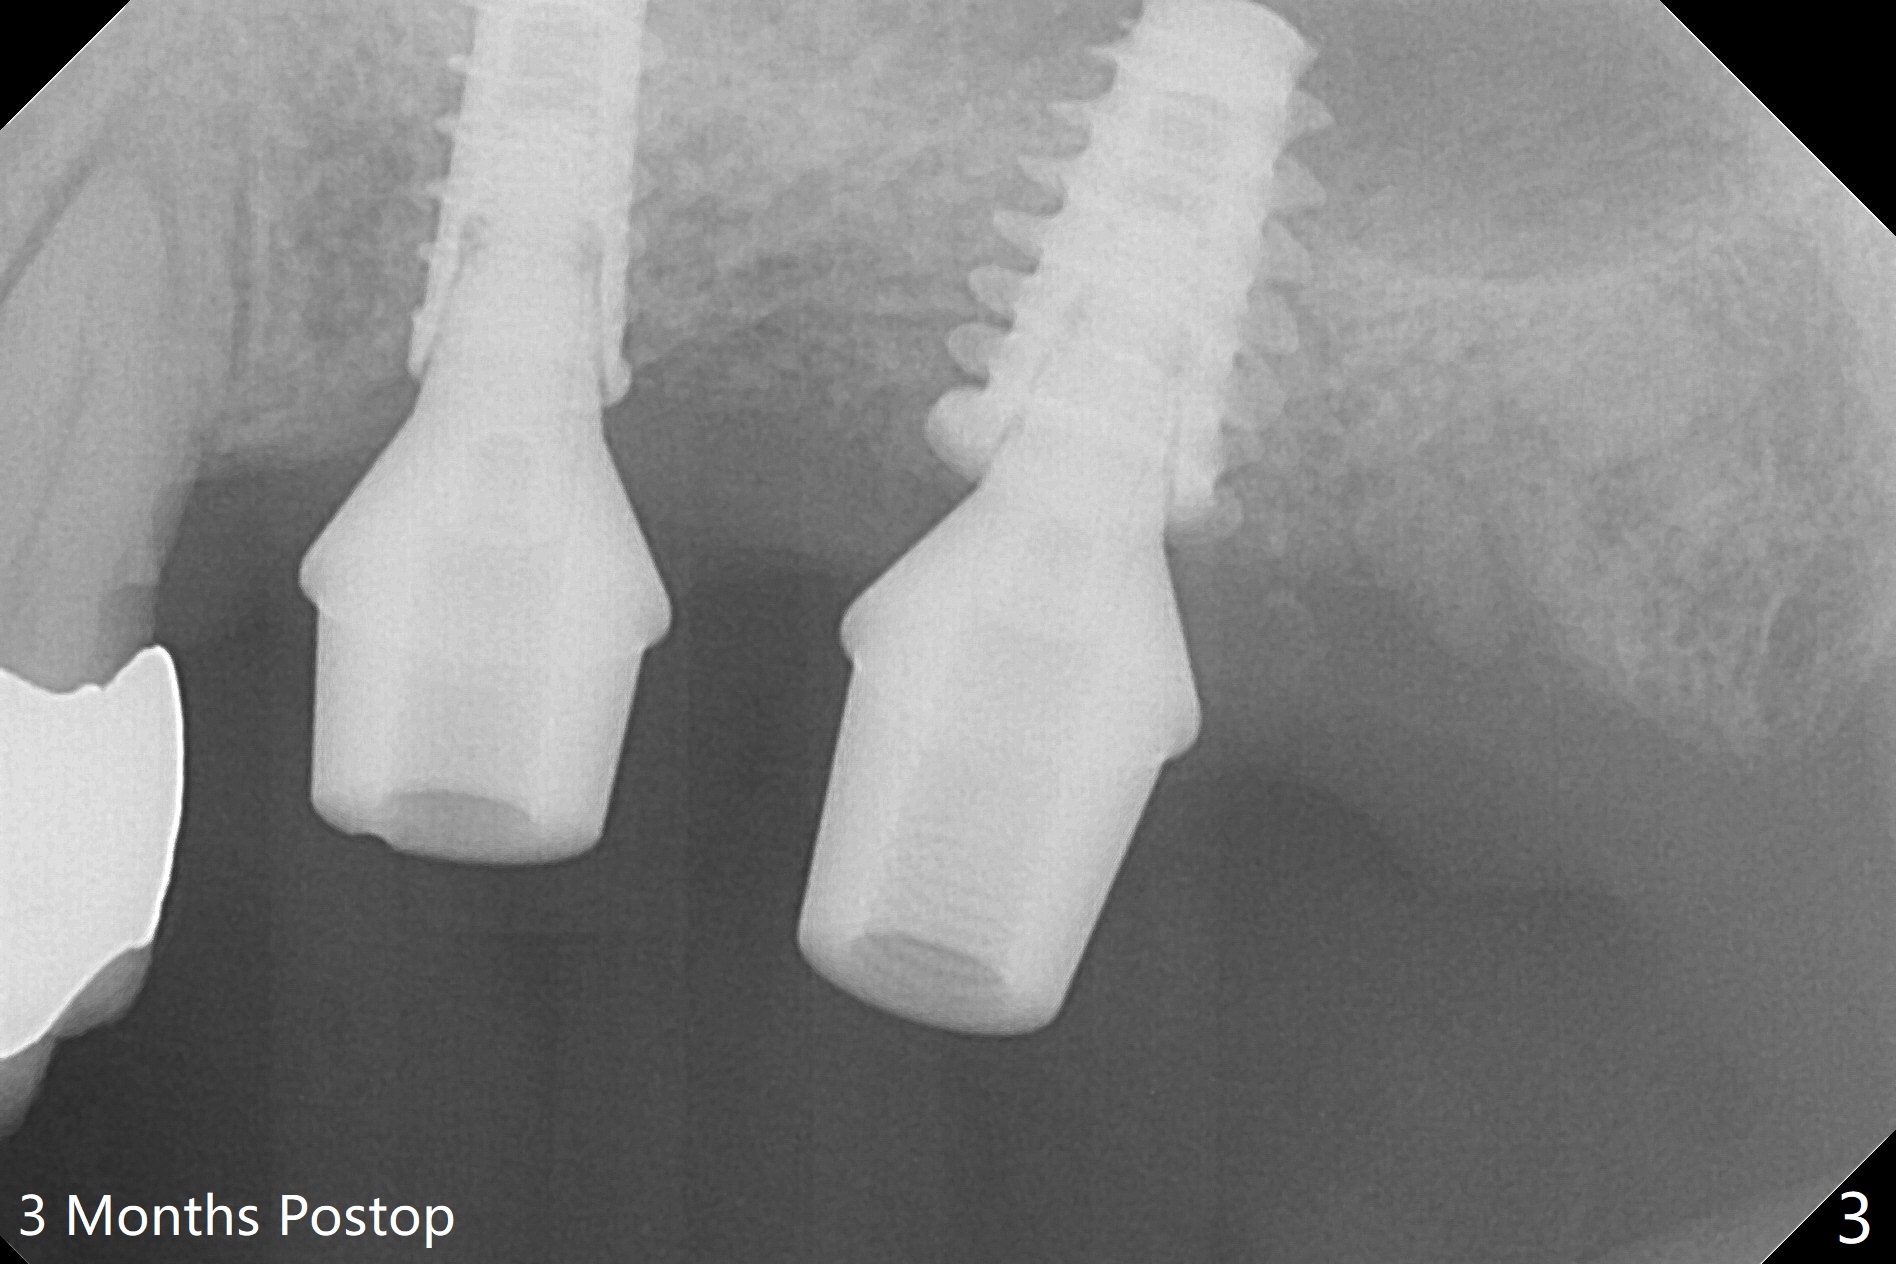

Due to irregular shape of freshly extracted socket at #15, control of depth is difficult. The sinus membrane is perforated after use of bone spreader, probably associated with drills longer than expected. SM taps (5.0 and 5.3 mm) do not achieve stability. When a 5.5x9 mm IBS dummy implant is inserted, initial stability is obtained (Fig.1). Osteotomy at the edentulous area of #14 is uneventful with insertion of a 4x11 mm dummy implant (without involving the sinus floor apparently clinically as well, Fig.1). After adjustment of trajectory, a 4x11 mm definitive implant is placed at #14 with ~ 35 Ncm, while a 6x9 mm implant is placed at #15 with ~35 Ncm (Fig.2 (*: Vanilla Graft with Osteogen)). Periodontal dressing is applied around the abutments and neighboring teeth. There is mild oral and nasal hemorrhage postop. In fact the patient has history of stroke with oral Plavix intake. The medicine stops 4 days preop and is advised to resume after hemostasis is achieved. The patient returns 3 months postop (Fig.3). After changing abutments to 5.5x5.7(3) mm, impression is taken. The crown/abutment at #14 is loose 1 year 10 months post cementation. After use of 5.5 mm profile drill, the crown/abutment is reseated, but the seating is incomplete (Fig.4 <) because of contact of the abutment with the mesial crest (*). A larger profile drill does not help (Fig.5). When a narrower abutment (4.5x7.5(3) mm) is torqued, it appears to be completely seated (Fig.6). After distal surface adjustment of the abutment, impression is re-taken. There are 3 other unfavorable conditions: poor crown/implant ratio and trajectory and #18 missing. The abutment at #14 must have been prepared for parallelism before impression. Return to Upper Molar Immediate Implant, Prevent Molar Periimplantitis (Protocols, Table), Armaments No Deviation Prevent Screw Loosening Xin Wei, DDS, PhD, MS 1st edition 11/28/2017, last revision 02/23/2021